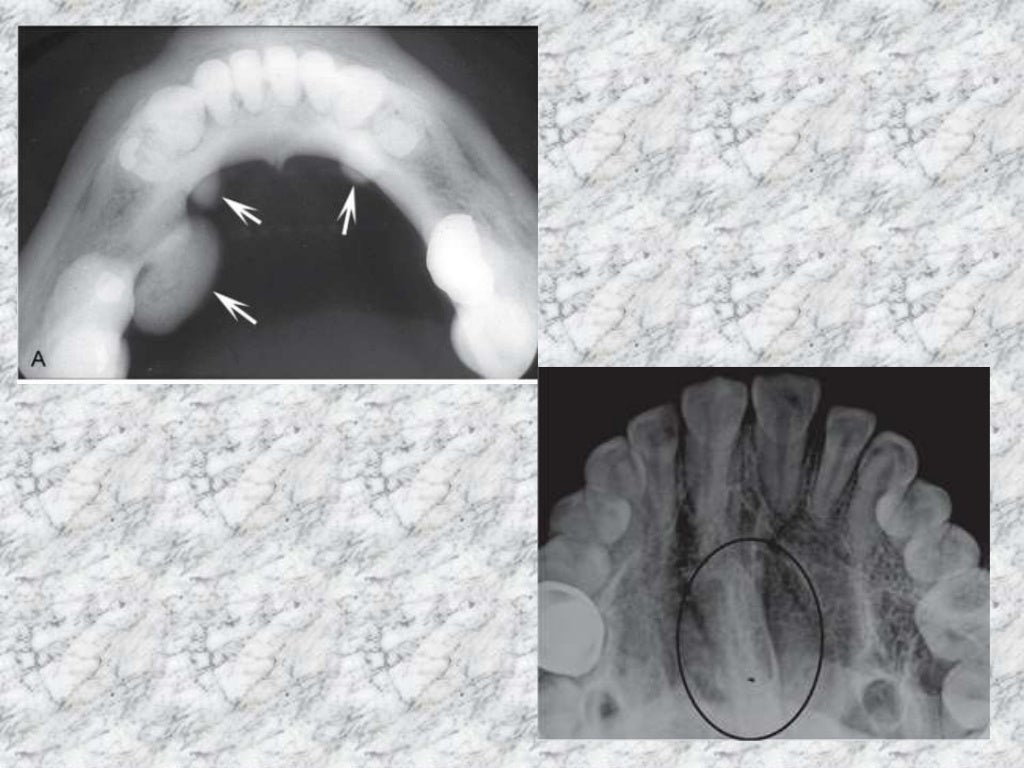

Mixed radiopaque & radiolucent lesions of jaw Most Radiopaque Nonodontogenic radiolucencies tend to be. What is the most radiopaque. What is the most radiolucent material? periapical radiolucencies are most commonly odontogenic. by understanding the significance of radiopaque materials in imaging processes, both healthcare. The radiopacity values of gradia direct loflo, dentin and estelite flow q were close to that of 1 mm al. what determines an. Most Radiopaque.